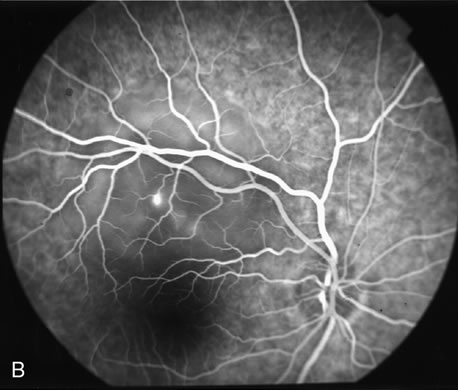

Gentamicin and tobramicin toxicity, which often result from inadvertent injection into the vitreous during cataract surgery, cause devastating retinal damage. In areas where high concentrations of gentamicin reach the retina there is obliteration of the retinal vasculature and ischemic necrosis of the retina (Fig. 43).269,270